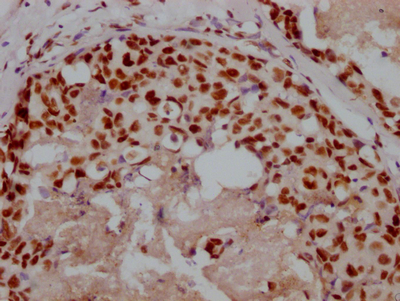

圖片:

The image on the left is immunohistochemistry of paraffin-embedded Human breast cancer tissue using CSB-PA969280(IRS2 Antibody) at dilution 1/100, on the right is treated with synthetic peptide. (Original magnification: ×200)